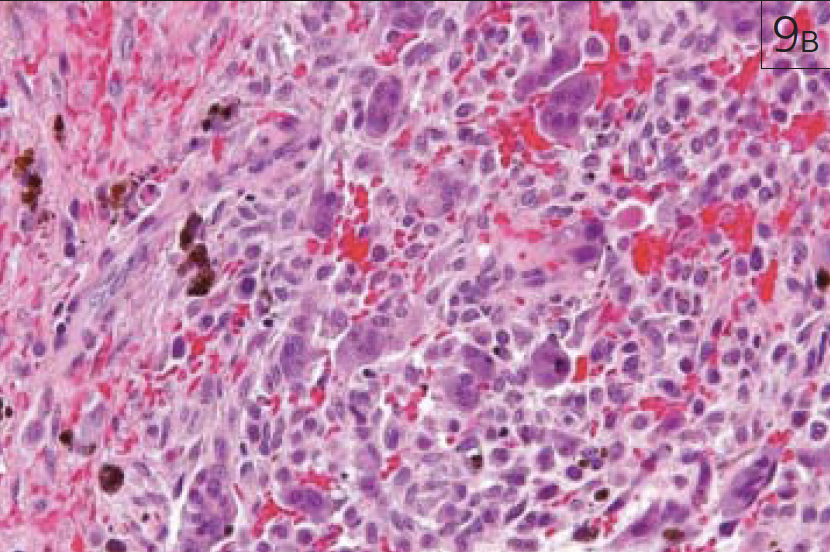

Патология костной ткани может характеризоваться не только изменением ее структуры, но и изменениями прилежащих мягких тканей (рис. 9 а-в).

Рис. 9. Центральнаягигантоклеточная репаративнаягранулёма нижней челюстислева (зона патологическихизменений отмечена нарисунках красной стрелкой):а – аксиальная проекция МСКТ;б – аксиальная проекция МРТ,Т2 ВИ;

Рис. 9. Центральнаягигантоклеточная репаративнаягранулёма нижней челюстислева (зона патологическихизменений отмечена нарисунках красной стрелкой): в – гистологическийпрепарат опухоли, окрашенныйгематоксилином и эозином,увеличение 200:1